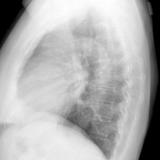

Case 1 PA

Peric calcification